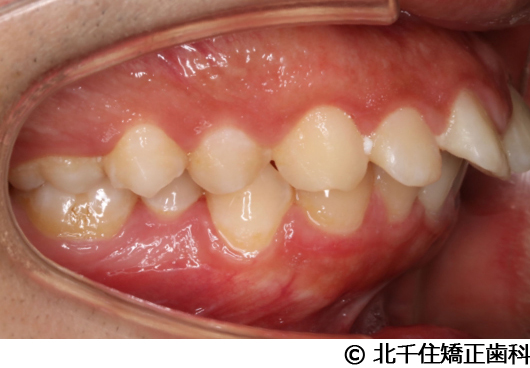

【症例5】上顎前突

- 治療前

- 治療後

- 治療名

- 上顎前突

- 費用

- 1,263,600円(税込)

- 期間

- 2年8ヵ月

- 治療回数

- 32回

- 通院頻度

- 1ヵ月ごと

- 年齢

- 13歳3ヵ月(初診時)

治療内容

-

患者様の症状

主訴:出っ歯

治療方法

骨格性の上顎前突、ヘッドギアを併用して上下顎第一小臼歯4本抜歯してワイヤー矯正。

治療結果

骨格性上顎前突に対し、ヘッドギアおよび抜歯を併用した矯正治療により歯列および咬合関係の調整を行った症例である。

治療後は保定装置を使用し、歯列および咬合の安定維持を目的として定期的な経過観察を行っている。